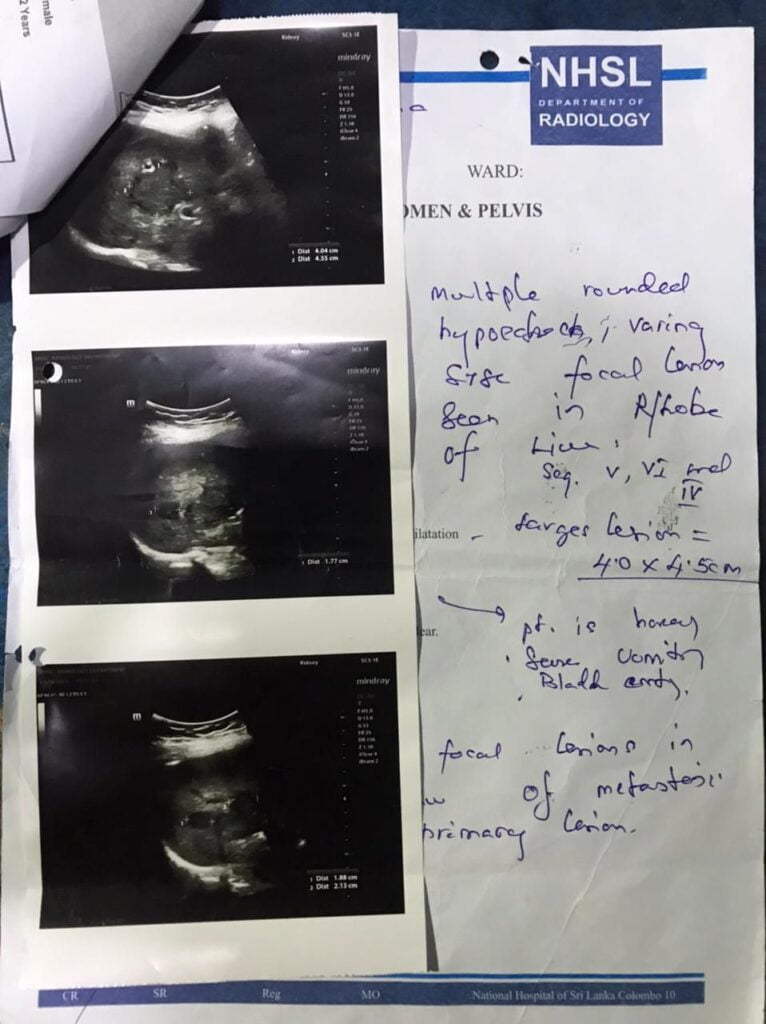

கேன்சர் நோயினால் பாதிக்கப்பட்டு சிகிச்சை பெற்றுவந்த நிலையில் தற்போது இவருக்கு நோய் பாதிப்பு அதிகரித்ததன் காரணமாக இவரைப் பரிசோதித்த வைத்திய நிபுணர்கள் இவருக்கு உடனடியாக PET-CT ஸ்கேன் சோதணயை செய்ய வேண்டும் என்றும் அரசாங்க வைத்தியசலையில் குறித்த ஸ்கேன் சோதணயயை செய்யும் இயந்திரம் பழது அடைண்த காரணத்தால் இந்தியாவில் உள்ள (MIOT) சர்வதேச மருத்துவமணையில் மேற்படி ஸ்கேன் சோதணயயை மேற்கொள்வதற்கு (500 K) 5 இலட்சம் ரூபா செலவாகும் என்றும் தெரிவித்துள்ளனர்.

குறிப்பு : இத்துடன் கேன்சர் நோயினால் பாதிக்கப்பட்டுள்ள N.S.N NAIMA நைமாவின் வைத்திய அறிக்கைகள் இணைக்கப்பட்டுள்ளன.